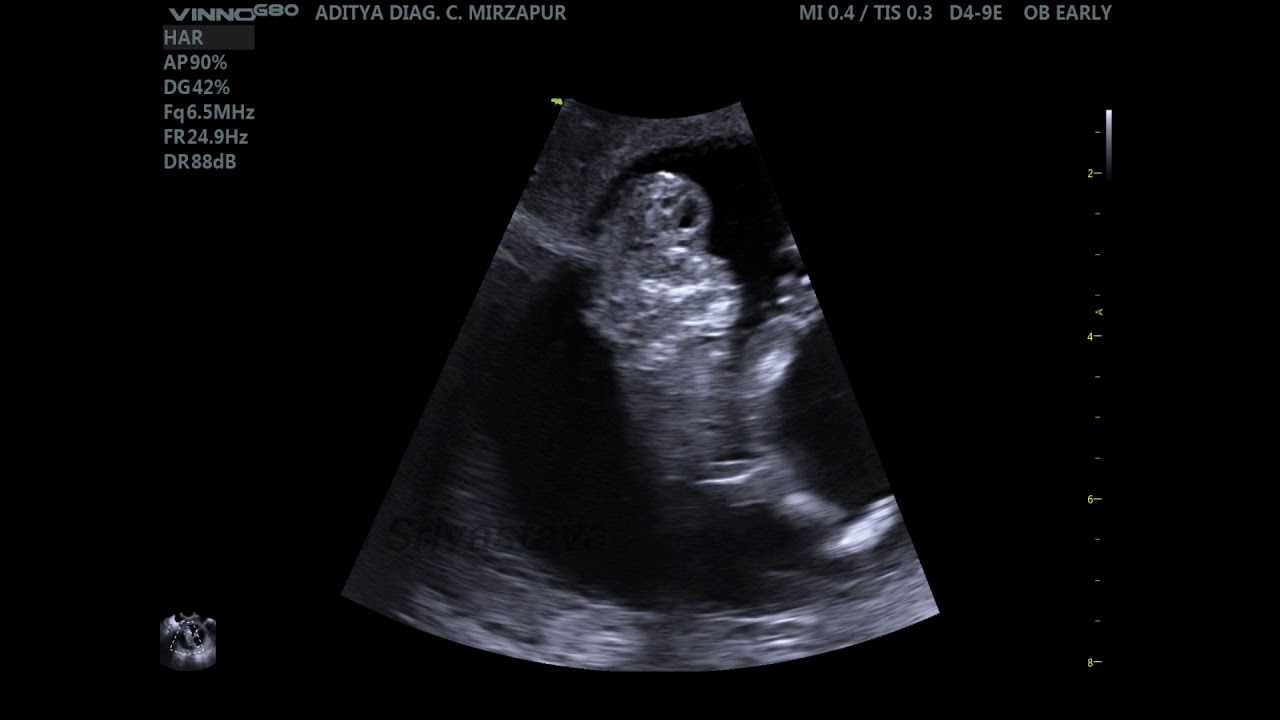

Данная аномалия развития, как уже замечено раннее несовместима с жизнью. Ребенок с акранией скорей всего рождается мертвым или умирает через короткий промежуток времени после рождения. На данное время существует единственный метод, который дает возможность поставить самый точный и достоверный диагноз – это ультразвуковое исследование, которое проводится после 10-ой недели беременности. В том случае, когда на мониторе врач отчетливо различает мозговую ткань, при этом главные костные ткани уже сформированы, тогда диагноз на 100% подтверждается. Но этот вид патологий не лечится. Диагностирование акрании плода, тут остается только показание к прерыванию беременности, поскольку шансов на жизнь у плода нет. Такая мера будет единственно правильным решением для матери и плода — пойти на искусственные роды, то есть аборт по медицинским показаниям.

Акрания является первичным событием, приводящим к более поздней последовательности экзэнцефалии и анэнцефалии. Хотя ранняя диагностика возможна (она была описана на 9-10 неделе беременности ), верно, что обнаружение до 14 недель затруднено, поскольку деформированная масса может напоминать нормальный мозг.